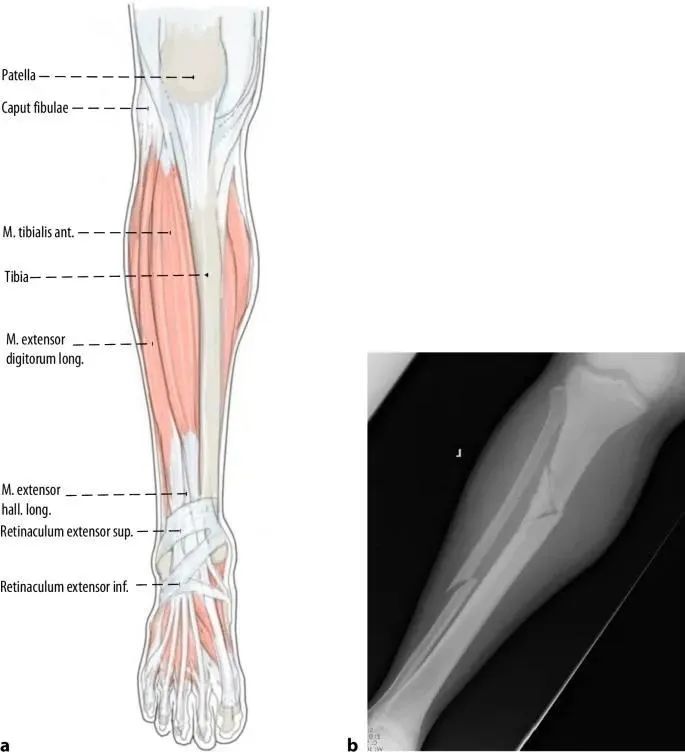

Основной причиной смещения при переломах проксимального отдела большеберцовой кости является деформация, вызванная натяжением сухожилия четырехглавой мышцы бедра при сгибании колена и механическим конфликтом между кончиком гвоздя и кортикальным слоем задней большеберцовой кости во время введения имплантата.Надколенник также предотвращает аксиальное введение гвоздя в сагиттальной плоскости (рис. 1а, б).Таким образом, другим распространенным методом доступа к точке является медиальный парапателлярный разрез, который приводит к небольшому медиально-латеральному введению гвоздя (рис. 1c и 2).Когда стержень входит в интрамедуллярный канал дистальнее перелома, его проксимальная часть наклоняется в сторону вальгуса (рис. 2).Наконец, напряжение мышц переднего отдела в состоянии покоя немного способствует вальгусной деформации (рис. 3).

Рисунок 1 a,b При использовании обычного инфрапателлярного доступа надколенник препятствует осевому входу стержня, что приводит к распространенной деформации переднего апикального сагиттального и вальгусного коронарного выравнивания.c Использование парапателлярного доступа для интрамедуллярного выравнивания стержня.